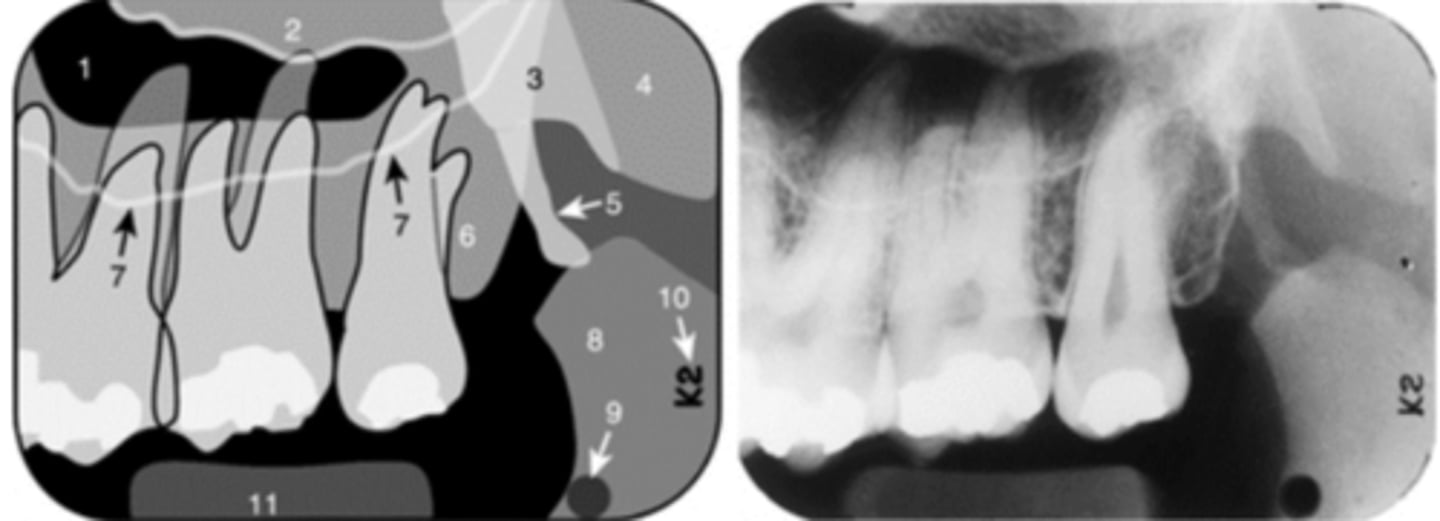

52

anterior border of the ramus

Name the structure the white arrow is pointing to.

<p>Name the structure the white arrow is pointing to.</p>

53

New cards

internal oblique ridge or mylohyoid ridge

Name structure the black arrow is pointing to.

<p>Name structure the black arrow is pointing to.</p>

54

Submandibular fossa

Name the radiolucent area indicated by the arrows

<p>Name the radiolucent area indicated by the arrows</p>

55

Floor of nasal cavity

What does the line indicated by the arrows represent?

<p>What does the line indicated by the arrows represent?</p>